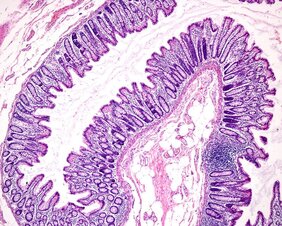

Gekrümmte Oberflächen finden sich überall in biologischen Geweben. Sie sorgen zum Beispiel für die vergrößerten Oberflächen, die für die Aufnahme von Nährstoffen im Darm oder für den Gasaustausch in der Lunge notwendig sind. Es gibt immer mehr Hinweise darauf, dass Zellen erkennen können, ob sie sich in einer flachen oder gekrümmten Umgebung befinden. Diese dreidimensionale Krümmung kann sich auf viele Prozesse auswirken, etwa auf die Bewegung von Zellen, die Entwicklung von Stammzellen und sogar auf den Verlauf von Krankheiten. Die zugrundeliegenden Mechanismen mit denen Zellen die Krümmung wahrnehmen sind jedoch weniger klar; auch wie dies letztlich ihr Verhalten bestimmt.

Gabrieles Team reproduzierte die in lebenden Geweben beobachteten Krümmungen auf sehr kontrollierte Weise. Es entwickelte eine Methode, um Zellen auf gekrümmten Oberflächen aus weichen Hydrogelen zu züchten. Hydrogele bestehen aus langen Molekülketten, die Wasser zwischen sich speichern. Diese Herangehensweise vereinfachte das komplizierte Problem, die Auswirkungen der Krümmung in komplexen lebenden Geweben klar zu beobachten. Solche Gewebe haben viele Rückkopplungsschleifen, die ihre Entwicklung steuern und es schwierig machen, Ursache und Wirkung zu unterscheiden. Die speziell konstruierten Oberflächen haben Täler und Berge in der Größenordnung von einem Hundertstel bis zu einem Zehntel eines Millimeters. Die Experimente zeigten, dass die gezüchteten Zellen dazu neigen, sich auf den Gipfeln dünn auszubreiten und in den Tälern zu sammeln.